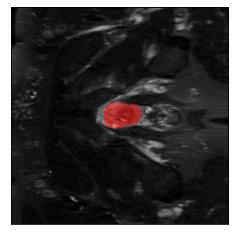

Machine learning models are typically deployed in a test setting that differs from the training setting, potentially leading to decreased model performance because of domain shift. If we could estimate the performance that a pre-trained model would achieve on data from a specific deployment setting, for example a certain clinic, we could judge whether the model could safely be deployed or if its performance degrades unacceptably on the specific data. Existing approaches estimate this based on the confidence of predictions made on unlabeled test data from the deployment's domain. We find existing methods struggle with data that present class imbalance, because the methods used to calibrate confidence do not account for bias induced by class imbalance, consequently failing to estimate class-wise accuracy. Here, we introduce class-wise calibration within the framework of performance estimation for imbalanced datasets. Specifically, we derive class-specific modifications of state-of-the-art confidence-based model evaluation methods including temperature scaling (TS), difference of confidences (DoC), and average thresholded confidence (ATC). We also extend the methods to estimate Dice similarity coefficient (DSC) in image segmentation. We conduct experiments on four tasks and find the proposed modifications consistently improve the estimation accuracy for imbalanced datasets. Our methods improve accuracy estimation by 18\% in classification under natural domain shifts, and double the estimation accuracy on segmentation tasks, when compared with prior methods.